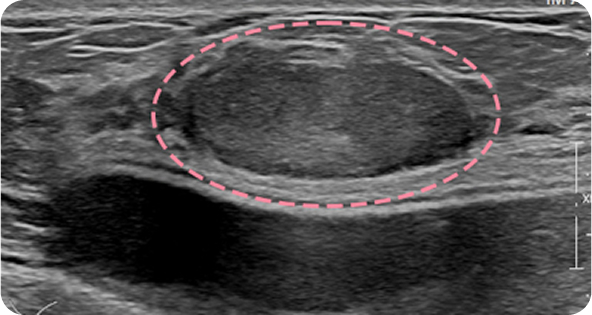

보형물 가슴성형 후 큰 유방 종양이 발견되었으나, 한송이 원장은 모든 시술 경력에서 단 한 번도 보형물을 건드리지 않은 고도의 숙련도로 맘모톰 시술을 안전하게 진행했습니다. 7개월 추적 검사에서도 내부 상태가 깨끗하게 유지되고 있습니다.